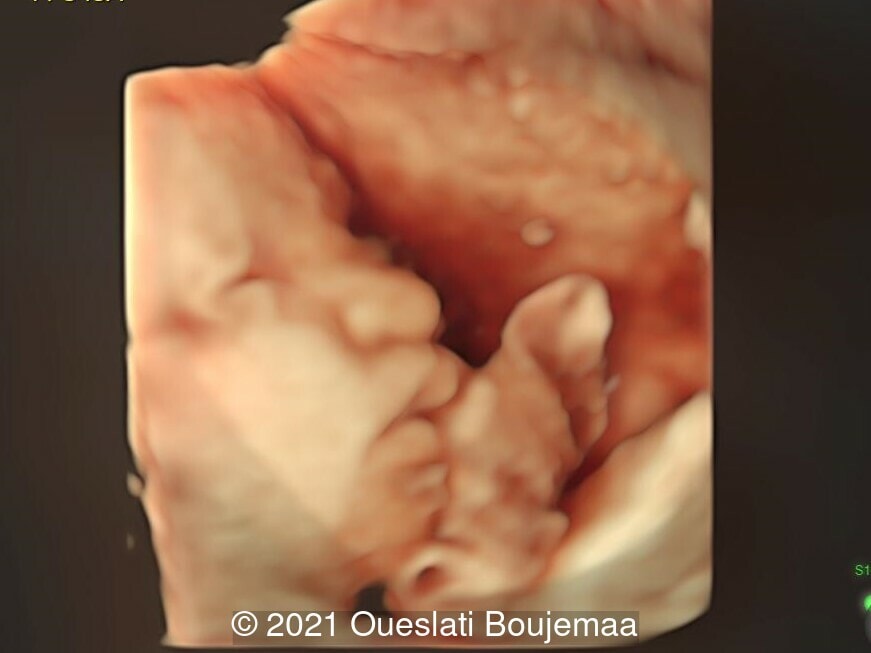

- Lower extremities show “sandal gap” (wider gap between the first and second toe), and rocker-bottom feet with prominent heels